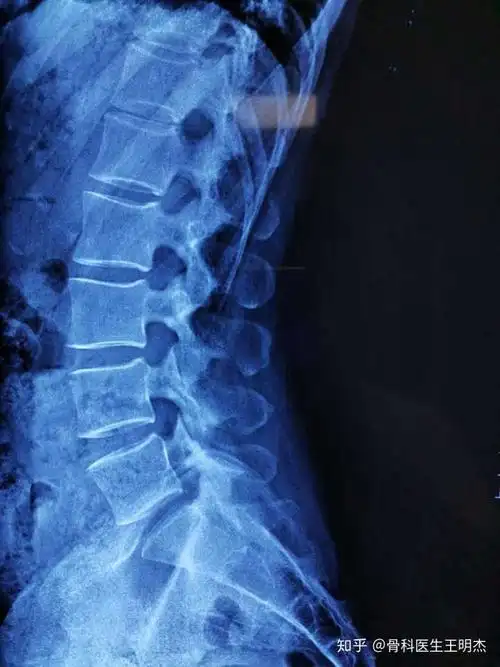

为什么颈椎生理曲度会变直会有什么严重后果吗

慢性腰肌劳损真的无法彻底根治吗?